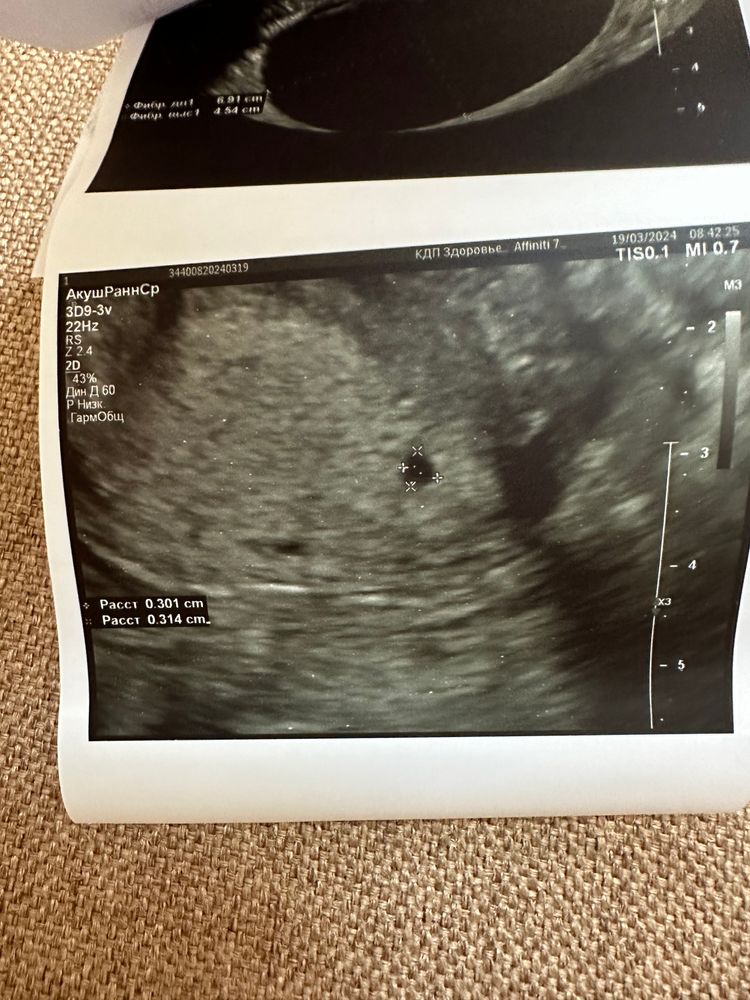

Поодное яйцо в углу матки

Посмотрите снимок узи, у кого так было, чем закончилось? Раньше писали матка седловидная, сейчас пишут нормальная

срок 4 недели , пя в левом углу матки, рядом еще одно под вопросом